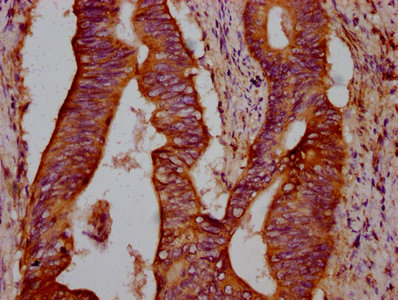

IHC image of CSB-PA615690LA01HU diluted at 1:300 and staining in paraffin-embedded human colon cancer performed on a Leica BondTM system. After dewaxing and hydration, antigen retrieval was mediated by high pressure in a citrate buffer (pH 6.0). Section was blocked with 10% normal goat serum 30min at RT. Then primary antibody (1% BSA) was incubated at 4°C overnight. The primary is detected by a biotinylated secondary antibody and visualized using an HRP conjugated SP system.